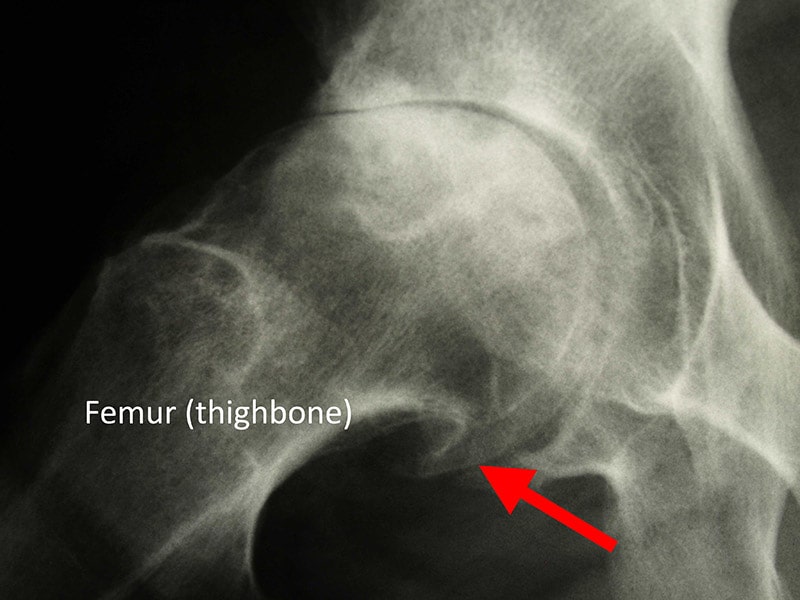

X-rays. X-rays provide detailed pictures of dense structures, such as bones. X-rays of an arthritic hip may show a narrowing of the joint space, changes in the bone, and the formation of bone spurs (osteophytes).

bone spur

In this X-ray of an arthritic hip, the arrow indicates a large bone spur (osteophyte) at the bottom of the femoral head.

Image courtesy of Stuart J. Fischer, MD, FAAOS